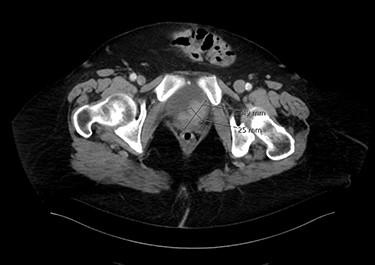

Eighty-year-old lady presented to the urology care with persistent dysuria and recurrent UTI. Cystoscopy showed mixed solid and papillary bladder tumour in the trigonal area and grossly normal bladder neck. Endoscopic resection confirmed muscle-invasive MPBC. Anterior pelvic exenteration with total urethrectomy was done. Pathology confirmed T4a micropapillary variant, infiltrating the vaginal wall and urethra. There was positive perivesical lymph nodes as well as positive bilateral iliac pelvic lymph nodes. Figure 1 shows an axial image of the bladder tumour.